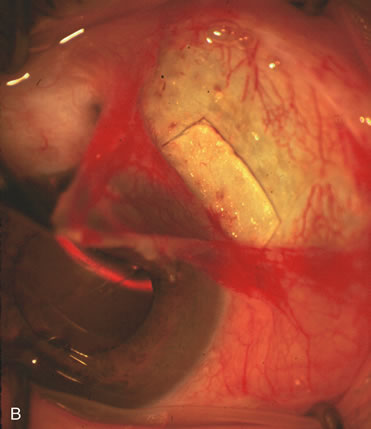

| EXTRACAPSULAR CATARACT EXTRACTION VIA NUCLEAR EXPRESSION COMBINED WITH GLAUCOMA FILTRATION SURGERY | ||||||||||||||||||||||||||||||||||||||||||||||||

| All patients are not candidates for phacoemulsification; thus, ophthalmic

Preparation of the Scleral Tunnel Creation of the scleral tunnel is a crucial step in successful wound construction. If the resultant scleral flap is too thin and a tear occurs during closure, excessive filtration with all the risks of hypotony will occur. When the scleral flap is too thick due to a deep plane, premature entry into the anterior chamber with subsequent intraoperative iris prolapse and bleeding occurs. During surgery, this results in a shallow anterior chamber with excessive iris and corneal trauma. Typically, a 50% to 75% depth flap seems to be safest for development of the flap and scleral tunnel. Additionally, if the scleral tunnel incision is extended too far into clear cornea, corneal striae inhibit adequate visualization during phacoemulsification. After achieving approximately 75% scleral depth, extend the scratch incision for 3 mm and use a crescent blade to tunnel 1 mm into clear cornea (Fig. 13). During development of the tunnel, keep the underside of the crescent blade flat against the curvature of the eye to establish the proper plane. Direct a 3-mm keratome to the end of the scleral pocket and with a dimpling-down maneuver enter the anterior chamber. This completes a triplanar incision, a critical prerequisite for small-incision wound stability.